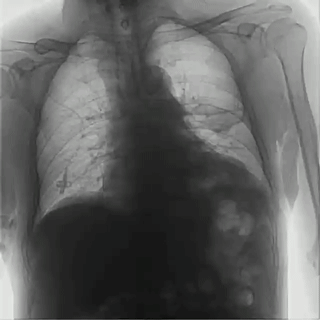

首先,具有可視化操作的功能,能通過(guò)多角度動(dòng)態(tài)影像觀察,瞬時(shí)高清點(diǎn)片,更好地發(fā)現(xiàn)病灶并進(jìn)行相關(guān)疾病的治療,解決了常規(guī)靜態(tài)DR不能解決的問(wèn)題,減少漏診誤診,提高臨床診斷的精準(zhǔn)性。

而且,影像采集幅面大,17×17英寸超大視野可覆蓋成年人的全胸全腹,并且能在連續(xù)動(dòng)態(tài)中實(shí)時(shí)高清點(diǎn)片,從而達(dá)到精準(zhǔn)診斷的目的。設(shè)備靈活高效的多維度運(yùn)動(dòng)設(shè)計(jì),也帶來(lái)了更加智能化、人性化操作體驗(yàn),可大幅提升檢查效率。